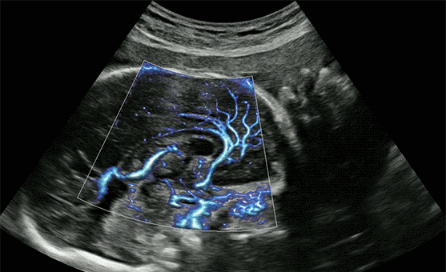

CrystalLive?是三星最新的超聲成像引擎,同時增強(qiáng)了2D圖像處理能力、3D渲染能力和彩色信號處理能力,能夠在復(fù)雜情況下提供出色的圖像性能,具備檢測外周血管、微循環(huán)血流的能力。